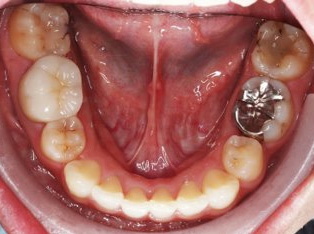

でこぼこがある状態になります。乱ぐい歯とも言われます。見た目がよくない審美障害が主な問題点ですが、その他にもでこぼこが多いことで、歯ブラシによる清掃性が悪くなり、結果、虫歯や歯周病のリスクも上がってしまいます。治療期間が短く済むことも多い為、気になった段階で早期に相談された方が良いと思います。

治療前

治療終了前